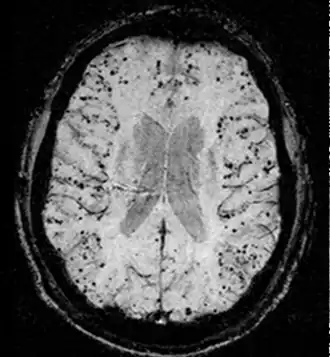

- Hémorragie cérébrale : la principale manifestation clinique de l'angiopathie amyloïde est l'hémorragie intracérébrale de topographie lobaire ou cérébelleuse[7]. La topographie lobaire regroupe les structures corticales et sous-corticales (c'est-à-dire proches de la surface du cerveau). Elle est principalement définie par opposition à la topographie profonde qui englobe essentiellement les ganglions de la base (en particulier le thalamus ou le noyau lenticulaire) et le pont. Cette distinction topographique est importante dans la mesure où l'hémorragie cérébrale lobaire est très évocatrice d'AAC alors que l'hémorragie cérébrale profonde est plutôt évocatrice de microangiopathie hypertensive. Cette distribution reflète l'atteinte préférentielle des petits vaisseaux corticaux dans l'AAC et de artères lenticulo-striées dans l'angiopathie hypertensive[8]. Cependant, parmi l'ensemble des topographies lobaires possibles, l'atteinte du lobe temporal ou occipital semble prédominante, en particulier si le patient avait déjà présenté une hémorragie dans ces régions[9]. Comme pour l'ensemble des AVC, les symptômes associés aux hémorragies cérébrales de l'AAC sont variables. Ils dépendent avant tout de la taille de l'hémorragie et de sa localisation.

- Manifestations neurologiques transitoires : l'AAC peut s'accompagner de troubles neurologiques - le plus souvent sensitifs ou moteurs - qui dans leur forme typique peuvent récidiver durant plusieurs semaines (« amyloid spells » dans la littérature scientifique anglo-saxonne). Le mécanisme exact de ces troubles reste inconnu et peuvent être aisément confondus avec des crises d'épilepsie focale ou des accidents ischémiques transitoires. À l'imagerie, ils sont souvent associés à la présence d'hémosidérose voire d'hémorragie sous-arachnoïdienne focale, ne touchant qu'un seul sillon cortical[10].

- Troubles cognitifs : la présence de troubles cognitifs spécifiques de l'AAC n'a été soulignée que récemment. Ceci explique un double facteur de confusion qui a pu masquer les troubles cognitifs propres à l'AAC : d'une part, la fréquente association clinique avec la maladie d'Alzheimer, d'autre part, le fait que l'AAC n'a souvent été étudiée que dans le cadre de l'hémorragie cérébrale, souvent responsable de troubles cognitifs potentiellement sévères par elle-même[11]. Néanmoins, il a été montré dans l'étude autoptique déjà mentionnée plus haut que la présence de lésions histologiques d'AAC est associée à un sur-risque de déclin cognitif indépendamment des autres lésions, en particulier celles de maladie Alzheimer[1]. Les études in vivo rendent plus difficile le contrôle de la part des troubles attribuables à la maladie d'Alzheimer. Une étude chez des patients ayant présenté une hémorragie cérébrale montrait un taux plus élevé de démence à un an chez les patients avec une hémorragie lobaire et de l'hémosidérose corticale et des microsaignements (trois signes clés à l'IRM du diagnostic d'AAC)[12]. Le profil cognitif propre à l'AAC est difficile à déterminer. Comparés à des patients souffrant de maladie d'Alzheimer, les patients avec une AAC (sans antécédent hémorragique) avaient des performances significativement meilleures sur les scores de mémoire épisodique mais comparables pour ceux des fonctions exécutives et de vitesse de traitement[13].

Le diagnostic de l'AAC se fonde sur les critères de Boston de 1995[14] modifiés en 2010[15]. Ces critères permettent de classer les patients en fonction du degré de probabilité du diagnostic. Le diagnostic de certitude est uniquement autoptique. Il est néanmoins possible de poser le diagnostic d'AAC possible ou probable du vivant du patient en s'appuyant sur un faisceau d'arguments essentiellement fondé sur les marqueurs hémorragiques à l'IRM cérébrale qu'il s'agisse de lésion en faveur d'une macrohémorragie cérébrale (> 1 cm de diamètre) ou de microhémorragie (diamètre < 1 cm).